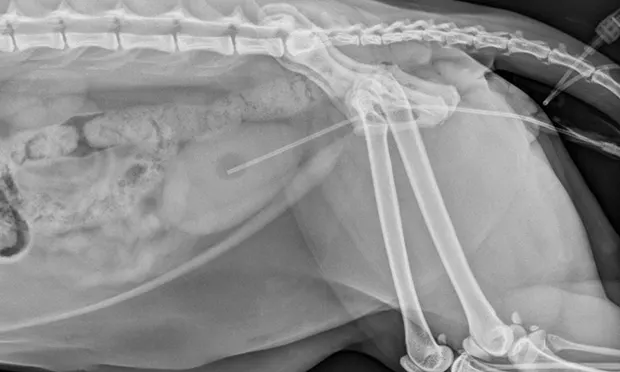

In addition to relieving the obstruction, life-threatening sequelae must be addressed. In complete urethral obstruction, the bladder distends until increased internal pressure results in necrosis and mucosal injury. This pressure is transmitted to the ureters and subsequently to the kidneys, exceeding the glomerular filtration pressure and resulting in azotemia, electrolyte derangements (eg, hyperphosphatemia, hyperkalemia), acidosis, and decreased urine production.

Unless the patient is unstable, urethral catheter placement is impossible or the bladder is distended to the point that the clinician feels uncomfortable flushing during unblocking, cystocentesis should be avoided. There is considerable risk for rupture if the large, distended, firm bladder–already at risk for pressure necrosis or mucosal injury–is pierced.